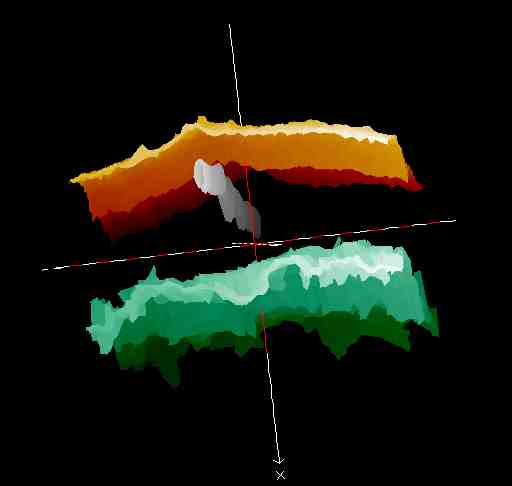

20 MHz 3D images

| Misc. |  Cellulite, arm |

Microdialysis tube |

Intradermal nevus |

Highlight. intrad. nevus |

| Misc. |  Ageband, forearm |

Nevus, skin parallel cut |

Normal, overlying hairs |